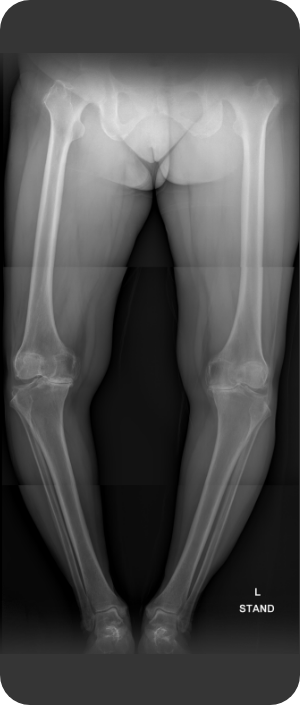

무릎인공관절 전치환술 사례1

• ▲ 수술 전

• ▲ 수술 후